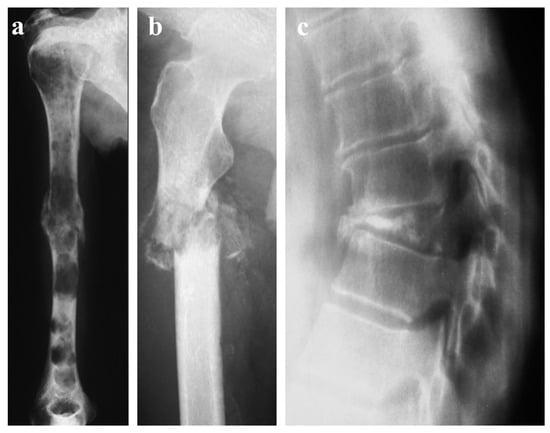

- Pilepich, M.V.; Vietti, T.J.; Nesbit, M.E.; Tefft, M.; Kissane, J.; Burgert, O.; Pritchard, D.; Gehan, E.A. Ewing’s sarcoma of the vertebral column. Int. J. Radiat. Oncol. Biol. Phys. 1981, 7, 27–31. [Google Scholar] [CrossRef] [PubMed]

- Reinus, W.R.; Gilula, L.A. Radiology of Ewing’s sarcoma: Ewing’s Sarcoma: Intergroup Ewing’s Sarcoma Study (IESS). Radi-ographics 1984, 4, 929–944. [Google Scholar]

- Emir, S.; Akyüz, C.; Yazici, M.; Büyükpamukçu, M. Vertebra plana as a manifestation of Ewing sarcoma in a child. Med. Pediatr. Oncol. 1999, 33, 594–595. [Google Scholar] [CrossRef]

- Kager, L.; Zoubek, A.; Kotz, R.; Amann, G.; Wiesbauer, P.; Dobrowsky, W.; Gadner, H. Vertebra plana due to a Ewing tumor. Med. Pediatr Oncol. 1999, 32, 57–59. [Google Scholar] [CrossRef]

- Patnaik, S.; Yarlagadda, J.; Susarla, R. Imaging features of Ewing’s sarcoma: Special reference to uncommon features and rare sites of presentation. J. Cancer Res. Ther. 2018, 14, 1014–1022. [Google Scholar] [CrossRef]